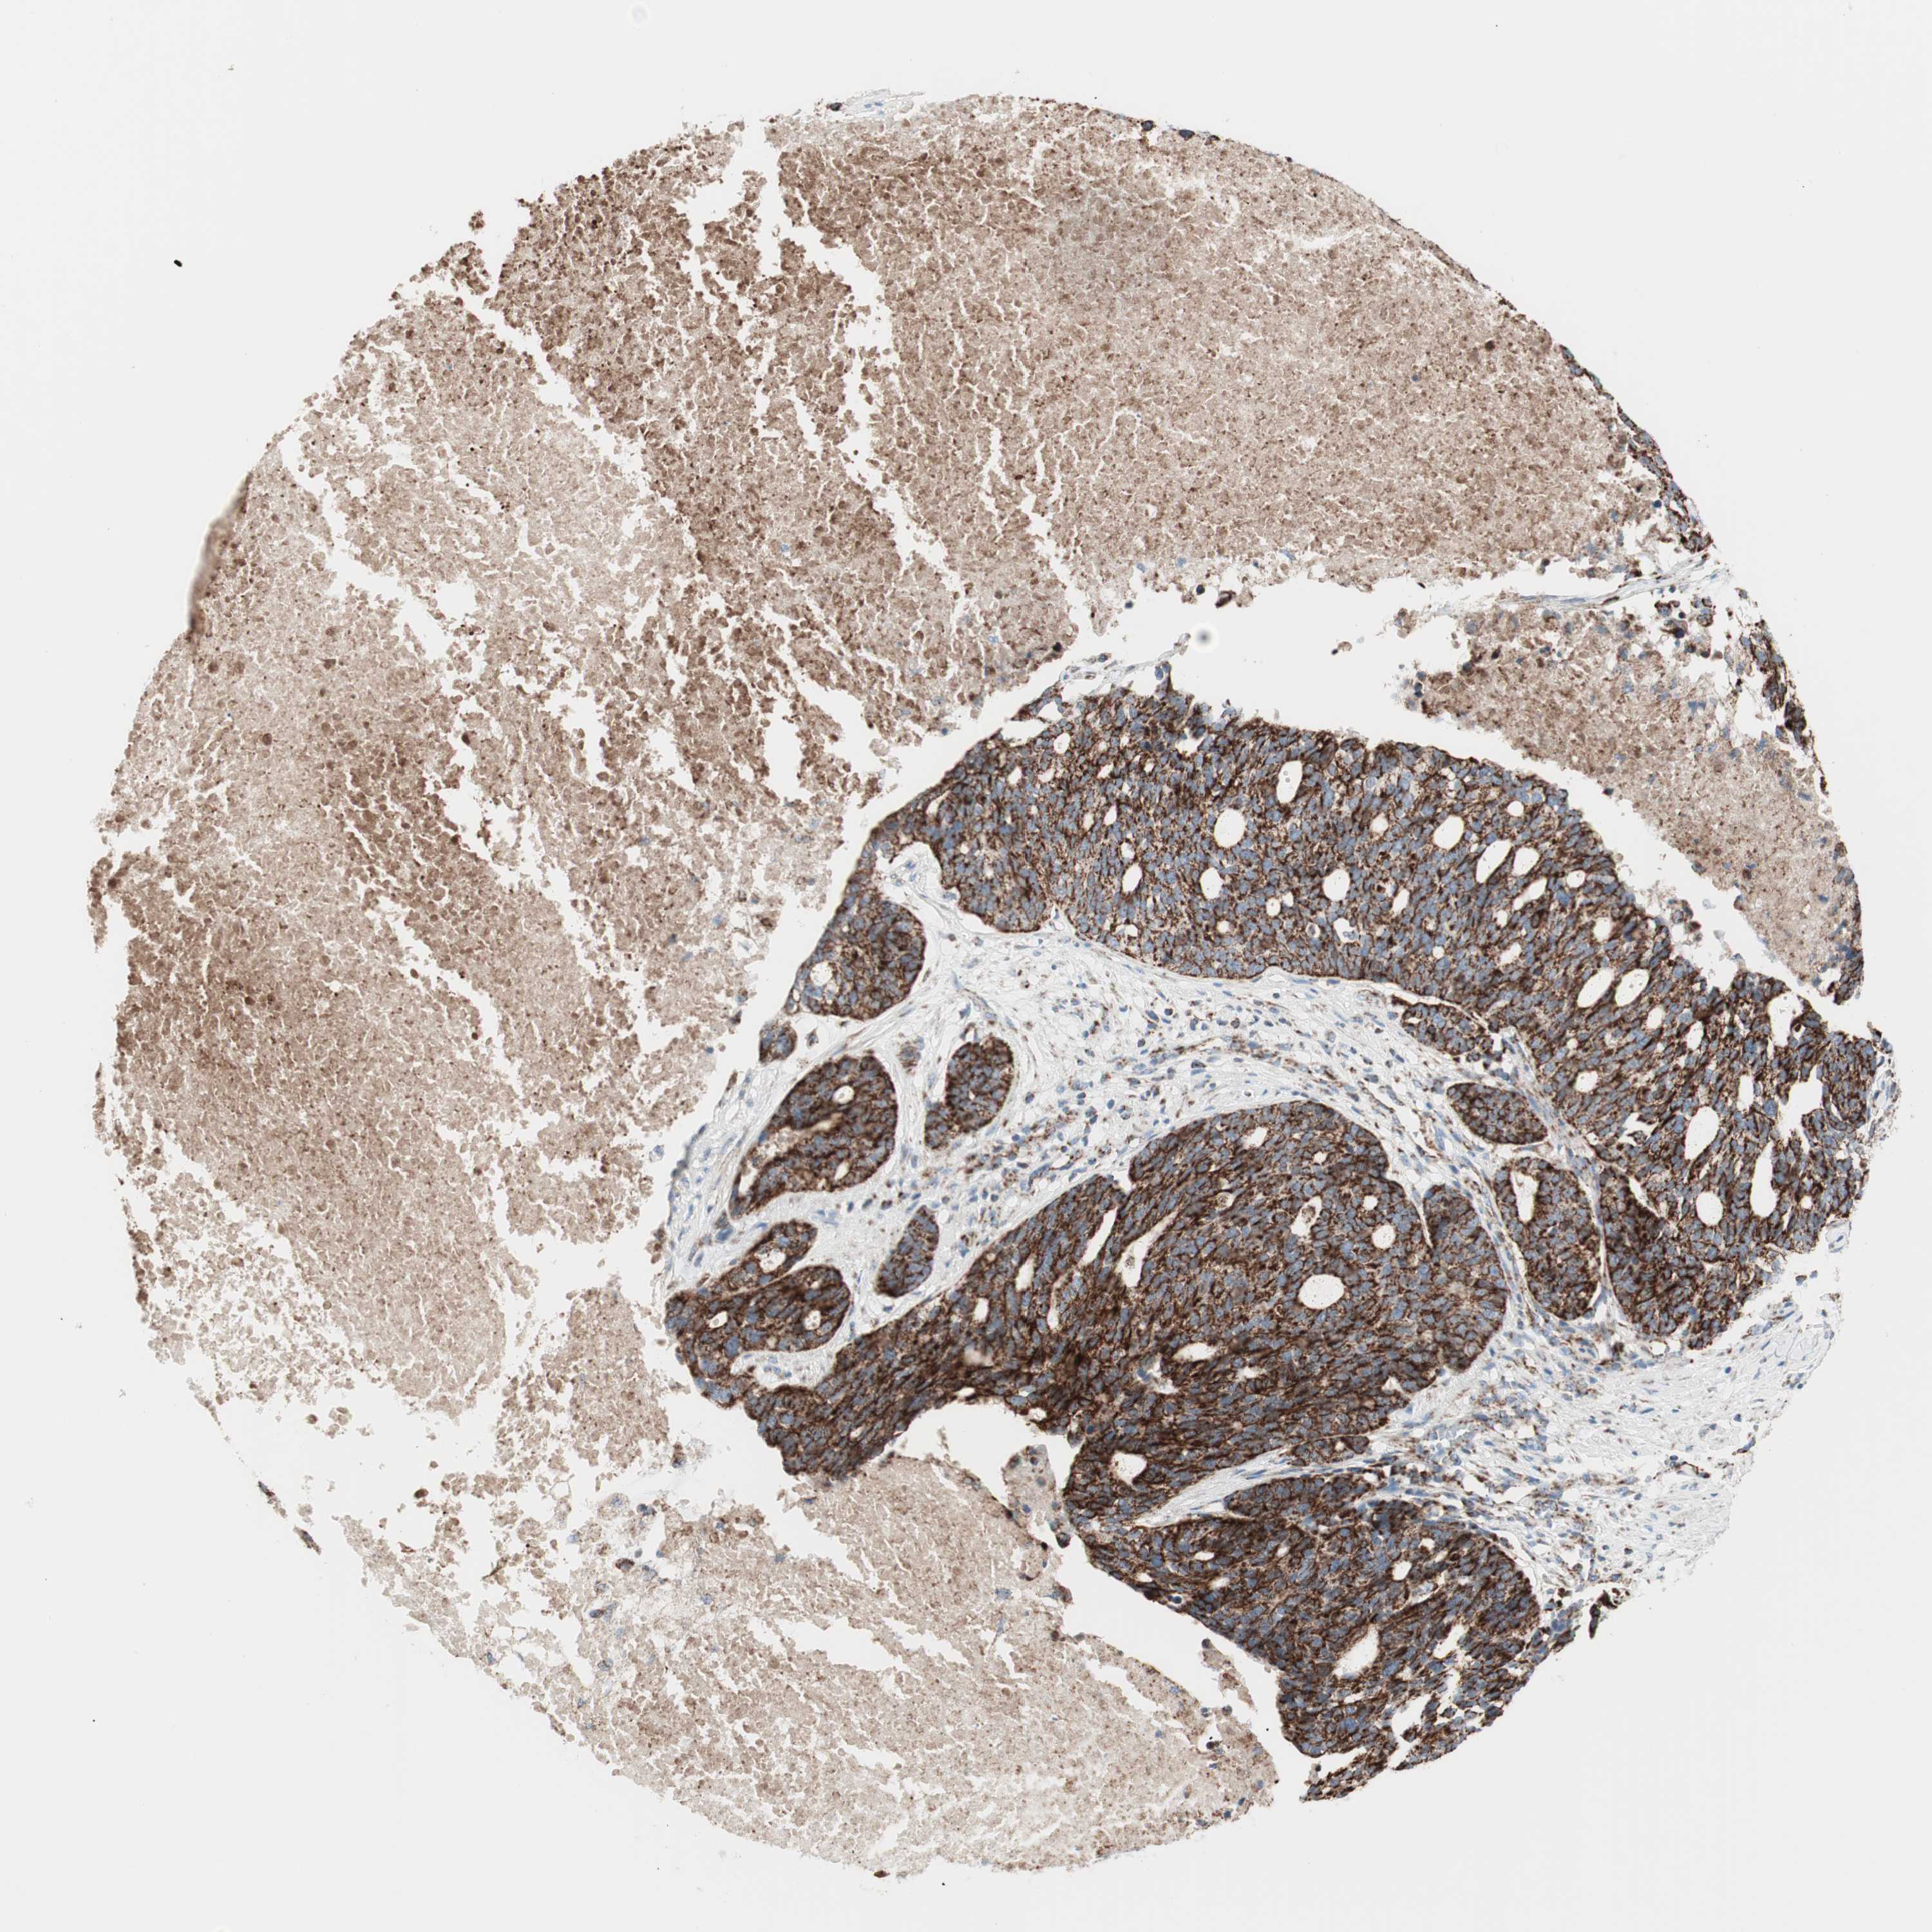

OVARIAN CANCER - Protein expressioni

A mouse-over function shows sample information and annotation data. Click on an image to view it in a full screen mode. Samples can be filtered based on level of antibody staining by selecting one or several of the following categories: high, medium, low and not detected. The assay and annotation is described here.

Note that samples used for immunohistochemistry by the Human Protein Atlas do not correspond to samples in the TCGA dataset.

Antibody stainingi

Antibody staining in the annotated cell types in the current human tissue is reported as not detected, low, medium, or high, based on conventional immunohistochemistry profiling in selected tissues. This score is based on the combination of the staining intensity and fraction of stained cells.

Each image is clickable and will lead to virtual microscopy that enables deeper exploration of all samples and also displays staining intensity scores, fraction scores and subcellular localization as well as patient and tissue information for each sample.

Antibody HPA011562

Antibody CAB005585

Staining

High

Cystadenocarcinoma, serous, NOS

Carcinoma, endometroid

Cystadenocarcinoma, mucinous, NOS

Carcinoma, NOS